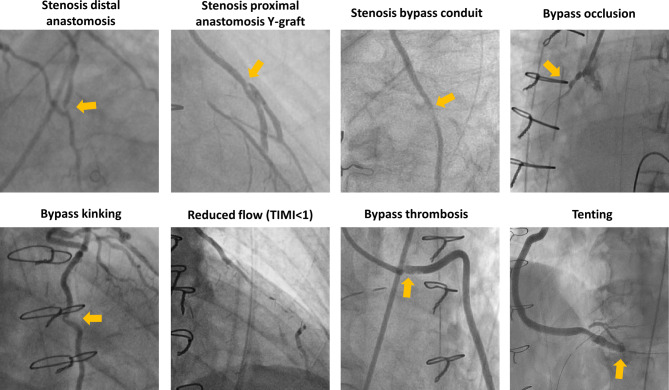

Methods: Patients who underwent clinically indicated coronary angiography (CAG) prior to post-CABG discharge between 2012 and 2022 were included. Symptomatic early CGF was defined as a dysfunctional coronary graft, evaluated on clinically indicated CAG, caused by stenosis of the proximal or distal anastomosis or bypass conduit, bypass occlusion, thrombosis, reduced flow (TIMI < 1) and kinking/tenting. Patients were divided into symptomatic early CGF and non-early CGF groups. Kaplan-Meier and multivariate analysis estimated cumulative survival free of major adverse cardiovascular events (MACE: death, myocardial infarction and revascularisation) up to 5 years' follow-up and identified predictors of symptomatic early CGF.